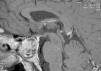

Radiographs of hands and feet (Figs. 3 and 4) showed an increase of soft tissue and joint space. In addition, the patient underwent laboratory analyses. We found serum growth hormone (GH) and IGF-1 were elevated: 5.67g/l (0–3.5g/l) and 121nmol/l (6.1–24, 8nmol/l), respectively. The patient was diagnosed with acromegaly. To complete the study she underwent a skull X-ray (Fig. 5) which featured an enlarged sella and a brain MRI detected the presence of a pituitary adenoma (Fig. 6).